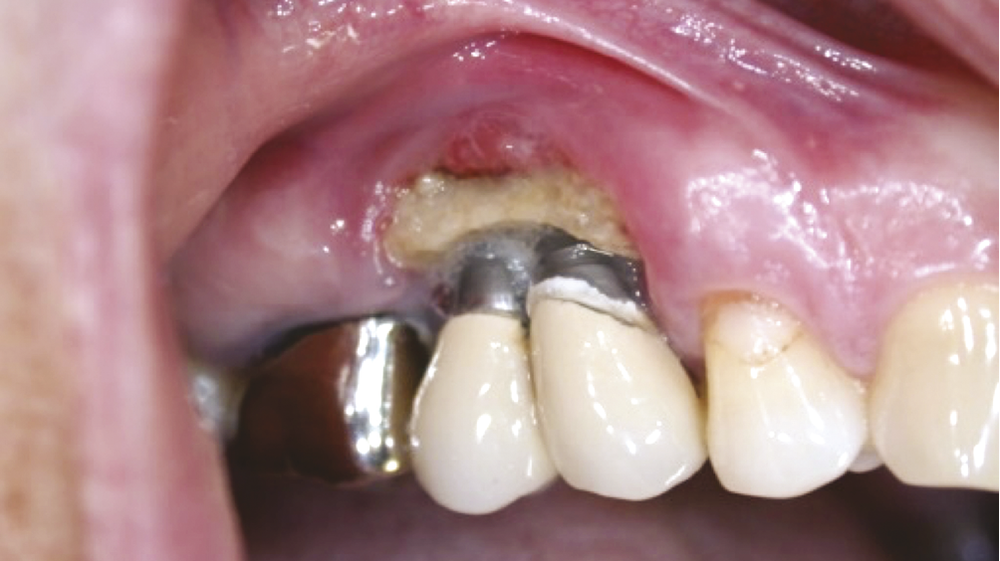

1. Dysplasie cémento-osseuse (DCO) de type floride au stade d’ostéomyélite.

2. Ostéonécrose après pose d’implant dans un contexte oncologique (BP IV cancer du sein).

• La dysplasie cémento-osseuse est une lésion fibro-osseuse rare de la mâchoire qui peut affecter certains secteurs (forme péri-apicale), ou les quatre cadrans (forme floride) (fig. 1). Au niveau radiologique, elle se caractérise dans cette dernière, par de multiples lésions osseuses denses et lobulées, souvent situées de manière symétrique dans plusieurs régions de la mâchoire (fig. 2). Ces lésions osseuses prédisposent au développement d’ostéomyélite maxillo-mandibulaire notamment en cas de geste invasif exposant l’os ou en cas d’infection dentaire. S’il est clairement contre-indiqué de recourir à la chirurgie implantaire dans les zones atteintes par la DCO, il pourrait en revanche être envisageable de poser des implants dans les zones indemnes [19,20].

• Certains inhibiteurs de la résorption osseuse que sont les bisphosphonates (BPs), ainsi que les anticorps monoclonaux anti-RANK-L (denosumab) sont à l’origine d’ostéonécrose des mâchoires (ONM) (fig. 2). Ces traitements sont indiqués à la fois dans des pathologies bénignes (ostéoporose, maladie de Paget, etc.) ou malignes (métastases osseuses de tumeurs solides, myélome) avec des risques d’ONM variables. Le risque est important dans les indications oncologiques, de l’ordre de 1 à 20 %, et nettement plus faible dans les indications bénignes, de 0,001 % à 0,1 % [23]. Il est actuellement contre-indiqué de réaliser la chirurgie implantaire chez des patients traités par des inhibiteurs de la résorption osseuse (BPs ou denosumab) dans des indications malignes. Pour autant, la chirurgie implantaire n’est pas contre-indiquée chez les patients traités par des BP per os ou du denosumab dans des indications bénignes, en l’absence de comorbidités et dans un temps de traitement de moins de cinq ans [23].